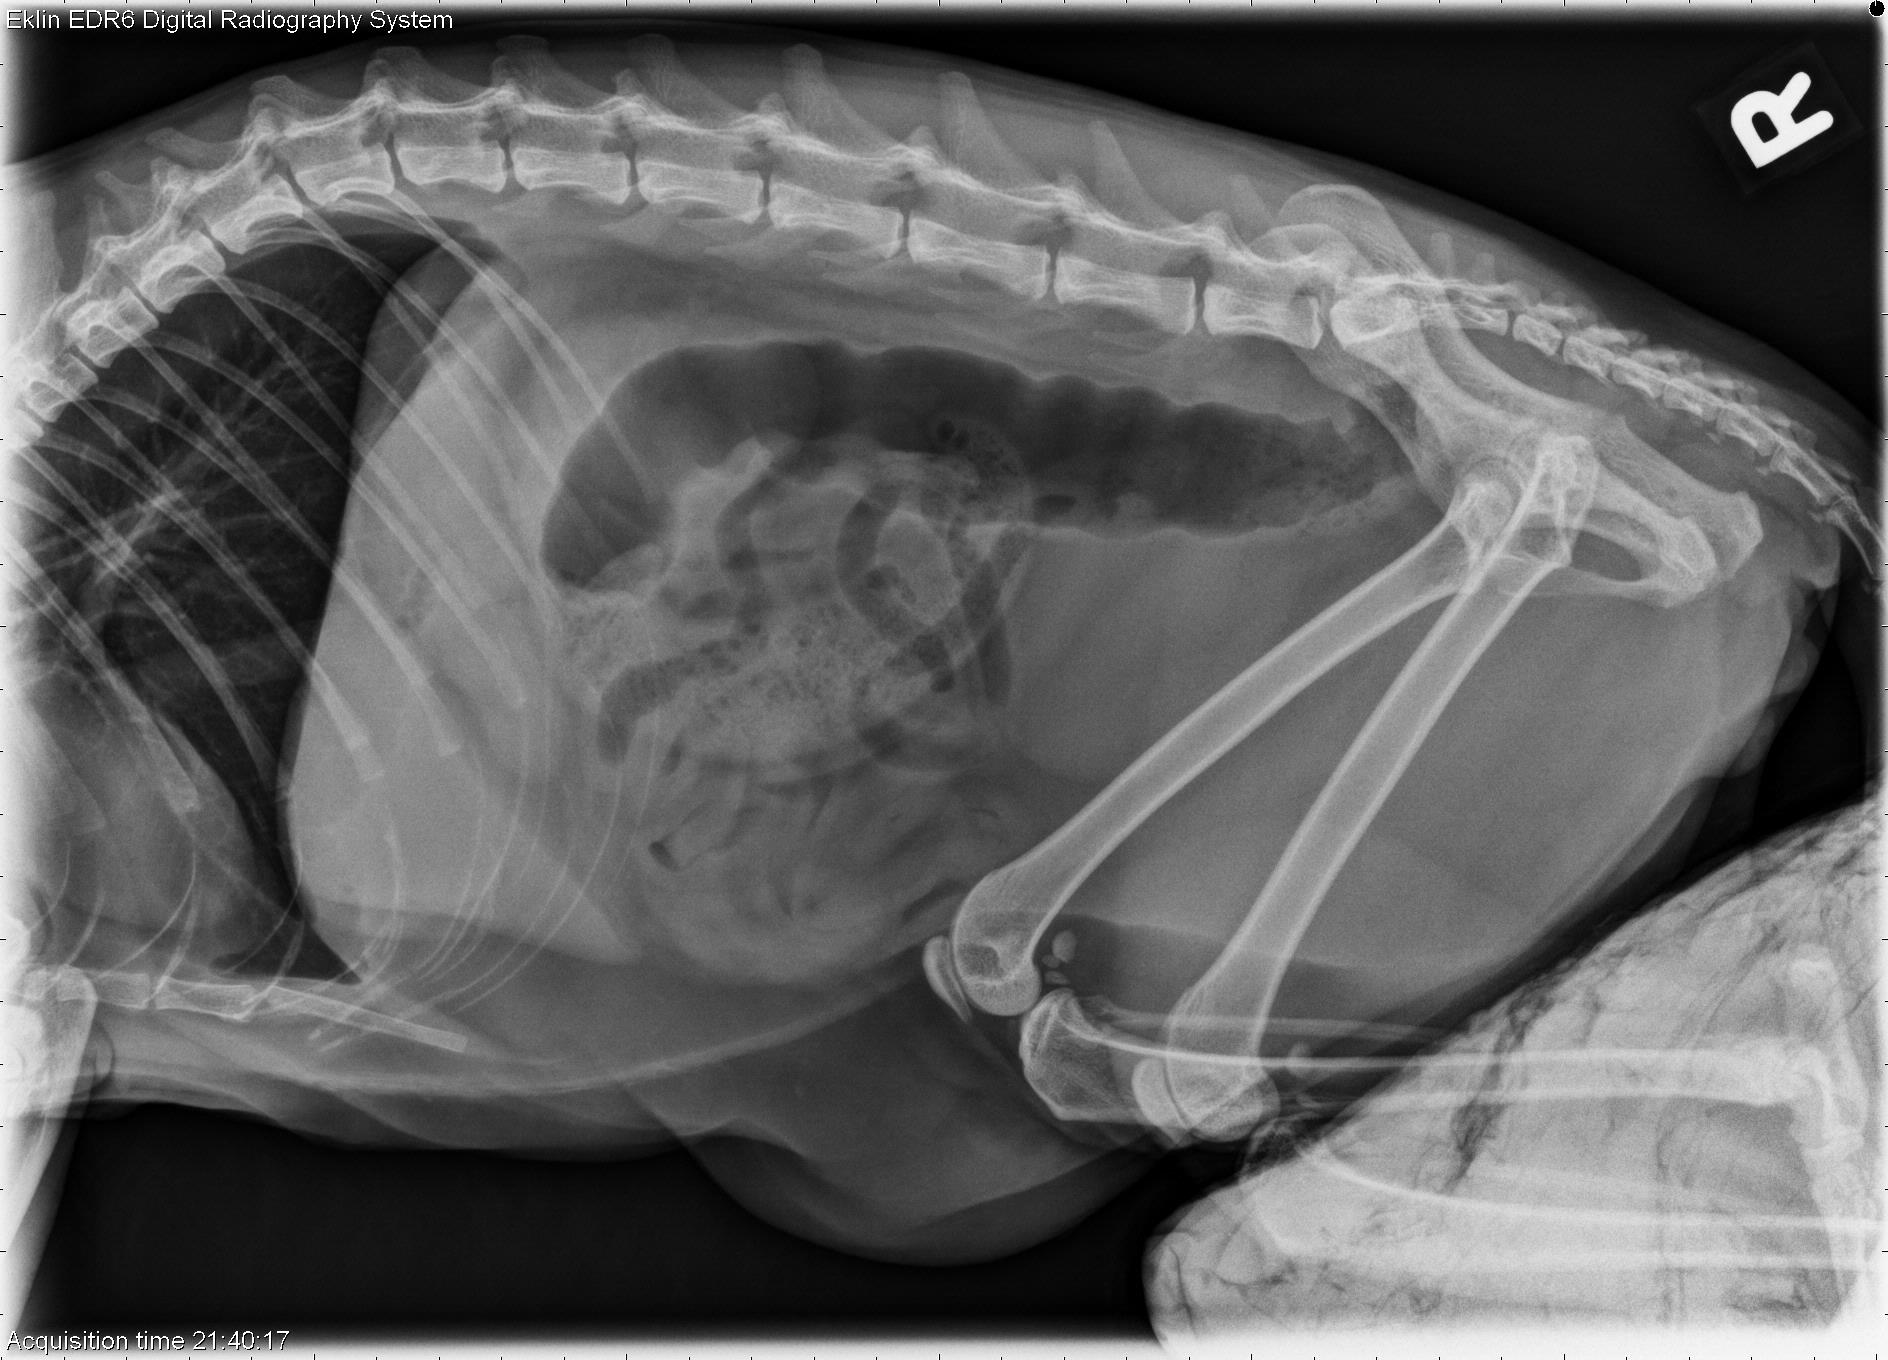

Today’s case is a 12-year-old domestic long-haired cat with decreased appetite and lethargy. This one is subtle. Does anyone see the abnormality?

On the lateral projections, there is gas superimposed over the gallbladder. The gas bubbles are faintly visible on the v/d projection lateral to the spine. The liver is moderately enlarged. The ascending colon is filled with fecal material, and the descending colon is empty. The remainder of the gastrointestinal tract is normal. No abnormalities are seen in the urinary tract. The spleen is moderately enlarged.

The hepatomegaly with focal gas collection may indicate an inflammatory process such as cholangiohepatitis, or a liver abscess. Ultrasound is recommended to further assess the abnormalities.

On ultrasound examination, gas was identified in the bile duct and biliary tree. No liver abscesses were identified. The cat improved with medical therapy and the gas began to resolve.